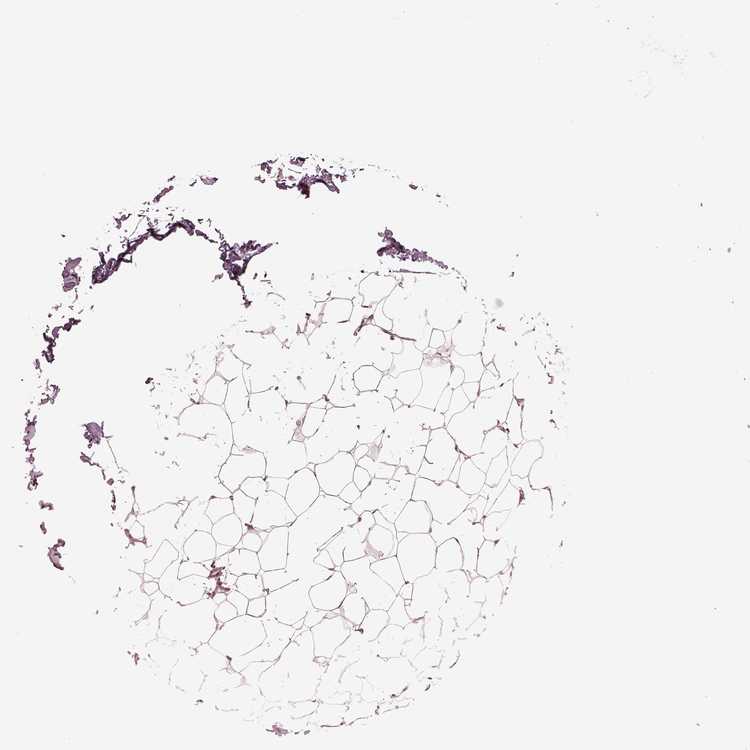

BREAST - Antibody stainingi

Antibody staining in the annotated cell types in the current human tissue is reported as not detected, low, medium, or high, based on conventional immunohistochemistry profiling in selected tissues. This score is based on the combination of the staining intensity and fraction of stained cells.

Each image is clickable and will lead to virtual microscopy that enables deeper exploration of all samples and also displays staining intensity scores, fraction scores and subcellular localization as well as patient and tissue information for each sample.

Antibody CAB004608

Adipocytes Low

Glandular cells High

Myoepithelial cells Low